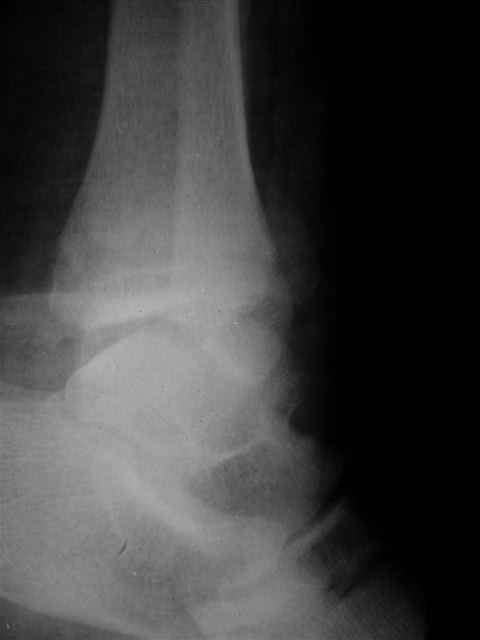

Отправитель: Evgueny Tschekashkin 16 Декабрь 2004, 09:24

В первом письме я упомянул о закрытом повреждении правого голеностопного сустава, эверсионно-пронационный механизм травмы - перелом внутренней лодыжки( поперечный, на уровне суставной щели) и отрывной перелом бугорка Chaput. После обработки открытых переломов бедра и большеберцовой кости в эту же сессию перелом внутренней лодыжки фиксировал двумя расходящимися спицами, бугорок Chaput двумя тягловыми винтами 3,5 мм. Раны заживают благополучно. Учитывая повреждение наружной группы мышц, активное разгибание в голеностопном суставе ограничено. Пассивная + пассивно-активная мобилизация голеностопного сустава с физиотерапевтом.

Каких-либо вопросов по лечению травмы голеностопного сустава у меня не возникло,поэтому о дальнейших деталях лечения я не упоминал.

(Если вы заинтересовались, то Рг граммы представлю)

Отправитель: Evgueny Tschekashkin 19 Декабрь 2004, 23:02

Я предупреждал, что ничего сверхъестественного. Каюсь, что одна из спиц прошла несколько дальше, чем нужно было, но главное - перелом стабилизирован и больной работает суставом в полном объёме, несмотря на представленную раннее травму коленного сустава.